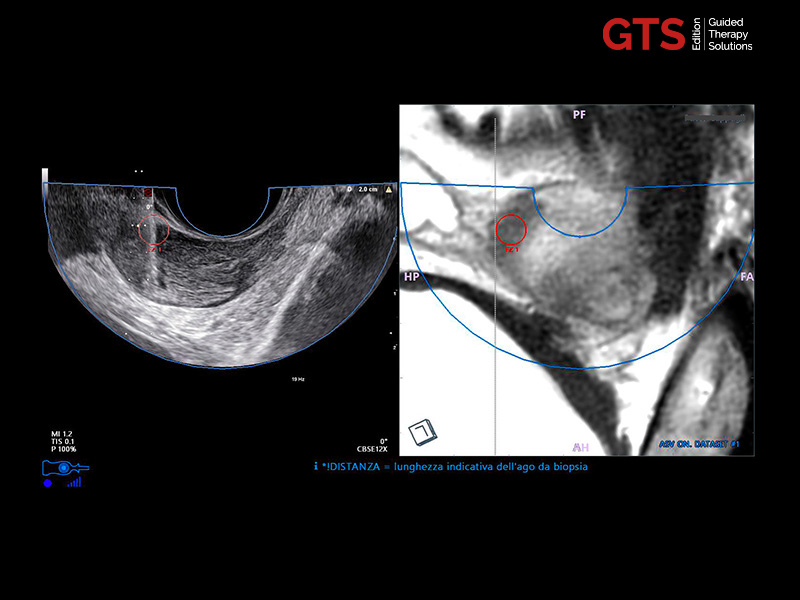

mpMRI targeting phase of PI-RADS 5 peripheral lesion